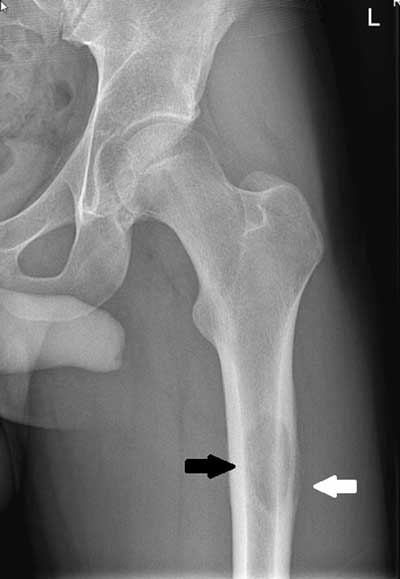

Pathologic Fracture

Occurs in bones already weakened by a pre-existing condition.

Bone Cyst

Wall of fibrous tissue filled with fluid - they are asymptomatic - appears as a lucent, oval shape with the long axis parallel to the host bone